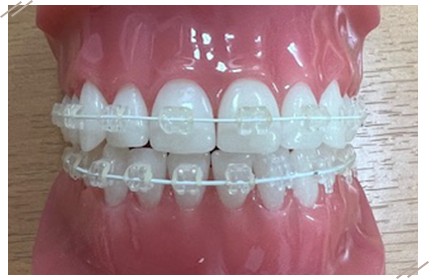

ワイヤー矯正でも、白や透明のブラケット、ホワイトワイヤーを使うことで目立ちにくくなります。費用と見た目のバランスを取りたい方に最適です。

特徴:自然な見た目/多くの症例に対応

注意点:完全に「見えない」わけではない